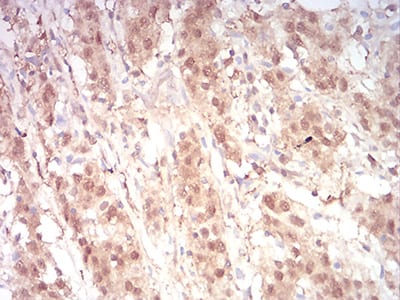

Immunohistochemical analysis of paraffin-embedded human stomach cancer tissues using RAN mouse mAb with DAB staining.

Immunohistochemical analysis of paraffin-embedded human cervical cancer tissues using RAN mouse mAb with DAB staining.